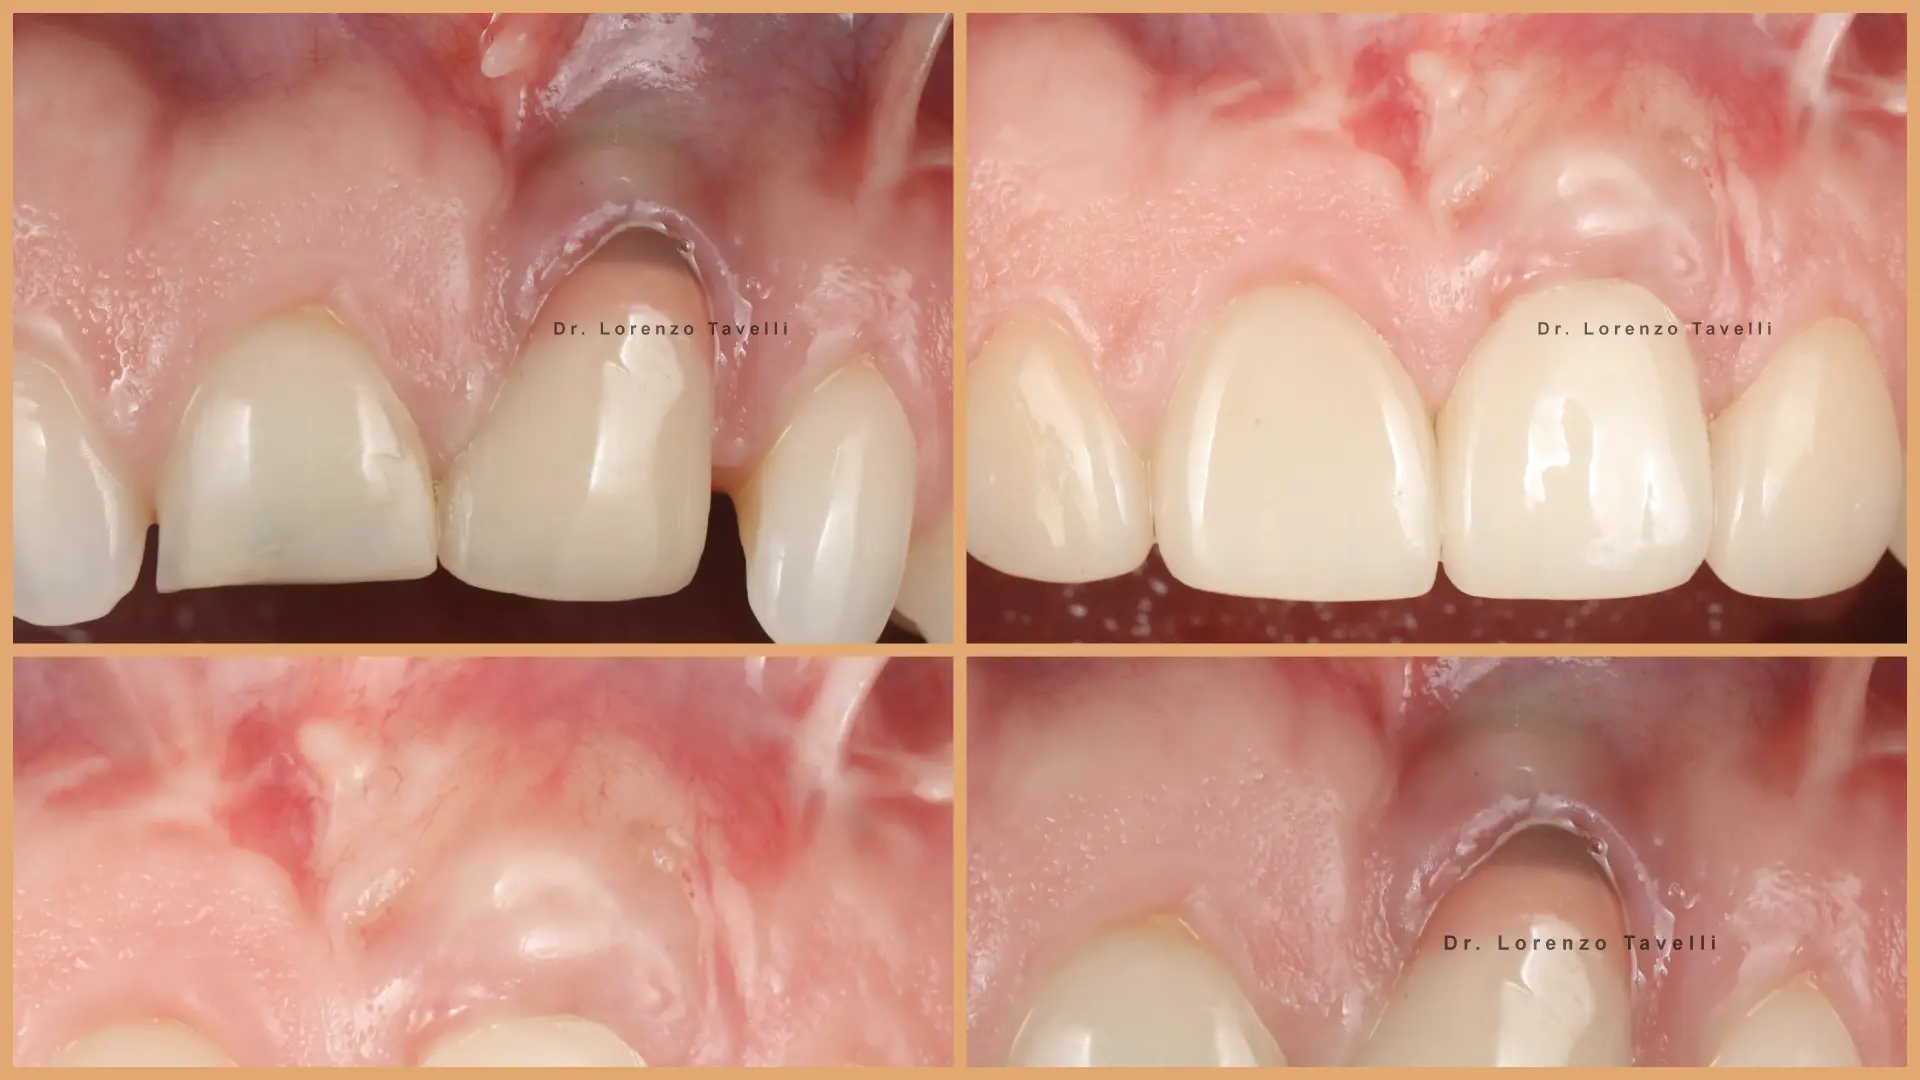

Prin prelegeri susținute de experți, videoclipuri chirurgicale și instruire practică (hands-on), participanții vor explora tehnici moderne de augmentare a țesuturilor moi, gestionarea fenotipului peri-implantar, prevenirea complicațiilor și protocoale avansate de grefare. O atenție deosebită este acordată tehnicilor minim invazive și de tip tunel, reconstrucției papilei și cazurilor complexe de implanturi în zona anterioară.

Până la sfârșitul cursului, participanții își vor extinde setul de abilități chirurgicale, își vor perfecționa procesul decizional și vor câștiga încredere în oferirea unor rezultate estetice previzibile pe termen lung în jurul implanturilor.

Implantologia estetică necesită mai mult decât precizie tehnică. Aceasta necesită o înțelegere profundă a biologiei, o execuție chirurgicală rafinată și capacitatea de a gestiona complicațiile cu încredere. Pe măsură ce așteptările cresc și cazurile devin tot mai complexe, clinicienii trebuie să își perfecționeze continuu abordarea pentru a obține rezultate stabile și cu aspect natural.

Atelierele noastre practice oferă participanților oportunitatea de a exersa tehnici contemporane de augmentare a țesuturilor moi și de grefare, sub îndrumarea experților. Prin sesiuni etapizate, aliniate cu scenarii clinice reale, participanții vor perfecționa abordările minim invazive și cele de tip tunel, reconstrucția papilei, gestionarea țesutului moale peri-implantar.

Acest curs este conceput special pentru clinicienii care doresc să își perfecționeze expertiza în implantologia estetică. Programul integrează în mod unic dovezile științifice cu aplicațiile practice, oferind o perspectivă exclusivă asupra unor cazuri clinice complexe prezentate de Dr. Lorenzo Tavelli, ce oferă o viziune aprofundată asupra parcursului său chirurgical personal și modul în care se iau cele mai bune decizii. La finalul cursului, veți dobândi un arsenal chirurgical extins și abilitățile necesare pentru a gestiona chiar și cele mai provocatoare situații în implantologie!